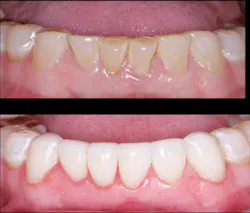

High caries activity-Presence of significant and obviously active caries usually indicates crowns over veneers. The margins of crowns placed slightly subgingival provide more caries resistance than supragingival margins in high caries-activity patients. Veneers are best when dental caries activity is not severe (figure 4).

Figure 4: Significant caries and tooth breakdown indicated that the best decision for these six maxillary anterior teeth was lithium disilicate crowns.